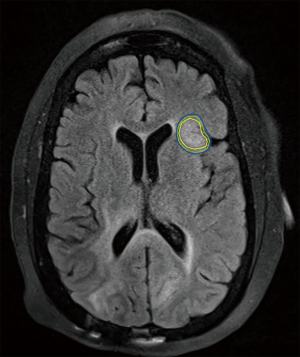

An area of controversy is the definition of a “limited” number of metastases when considering what is safe and practical for treating with SRS. Currently, the best evidence for treating patients with ≥4 metastases with SRS alone comes from the Japanese Leksell Gamma Knife Society, where patients with ≤10 brain metastases were treated with SRS alone. In this study, patients with a single brain metastasis had the best survival; however, patients with 5–10 metastases had an equivalent survival to those with 2–4 with similar rates of toxicities (25). Reports from the University of Pittsburgh suggest that treatment volume may be a more useful predictor of outcome after SRS than number of metastases alone (26,27). Given these studies, SRS treatment for >3 brain metastases has been adopted by the NCCN (28). An example of one such treatment utilizing Gamma Knife SRS is illustrated in Figure 1.

Regarding dose, the optimal dose-fraction scheme (i.e., single fraction vs. multiple fractions) for radiosurgery with brain metastases is unclear and there are no good comparisons between regimens. The doses most often used with single-fraction SRS are based on the findings of RTOG 90-05, which utilized maximum tumor diameter as a dose determinant (29). Tumor control appears correlated with the dose delivered, with local control rates for larger tumors typically lower than for smaller tumors. In these cases, a fractionated approach may be advantageous. In one retrospective analysis, patients with tumors >2 cm in diameter received either 27 Gy in 3 fractions or 15–18 Gy in 1 fraction, with the fractionated approach showing better local control (90% vs. 77% at 1 year) (30). Other fractionation schemes (35 Gy in 5 fractions, 36 Gy in 6 fractions, 40 Gy in 10 fractions) have been used with similar outcomes (31,32). In the post-operative setting, similar dosing schedules are used. The Stanford group recently reported on their phase I/II dose-escalation trial involving 3-fraction SRS and found that the maximum tolerated dose for 2–4 cm cavities was 27–30 Gy (33). The optimal approach utilizing SRS in the treatment of brain metastases continues to be an area of active investigation.